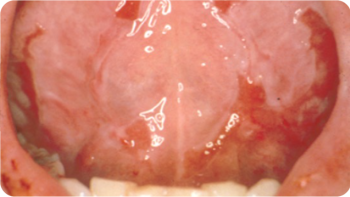

The Chemo Mouthpiece is a unique, easy-to-use oral cryotherapy device that helps minimize the occurrence and severity of chemotherapy-related oral mucositis, including discomfort, sores, ulcers and blisters in the mouth, giving adult chemotherapy patients comfort and relief from the pain and inflammation associated with mucositis.

The oral mucosa is the mucous membrane lining or “skin” inside of the mouth, including cheeks and lips. People with oral mucosal diseases may develop painful mouth sores or ulcers on this lining.